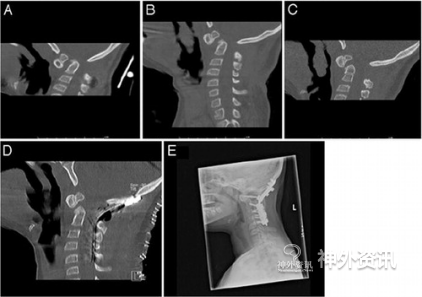

图3. A.治疗前CT矢状位显示移位的齿状突和腹侧脑干受压;B.穿戴Halo背心牵引系统10天后将牵引力提到13磅,驼背畸形和腹侧脑干受压明显缓解;C.28天后牵引力达到18磅,脊髓直径显著增宽;D.枕骨大孔减压术和枕骨-C5融合术后CT显示脊柱后突畸形已改善;E.术后2年复查CT示齿状突固定稳定。

病例2. 14岁女孩,诉逐渐出现运动困难而作MRI扫描,显示齿状突严重移位伴脑干腹侧受压和脊髓信号异常。四个月之后生活功能状况明显恶化,不能行走,大小便失禁。CT显示齿状突严重移位并压迫脑干腹侧。入院后给予Halo背心牵引系统治疗;穿戴4周,最大牵引力达25磅,齿状突后突畸形明显改善;MRI扫描见髓周空间增宽。随后行枕骨-C2融合术,C1侧块和C2椎板螺钉固定。术后患者神经症状明显好转,二便正常;在矫形器辅助下可独立行走,CT复查见齿状突后突畸形缓解(图4)。

图4. A.MRI-T2矢状位像示脊柱齿状突后突畸形明显并伴脊髓信号改变;B.6月后侧位平片示脊柱后突畸形加重;C.牵引10天牵引力达17磅,CT矢状位示后突畸形逐渐好转;D.牵引28天后牵引力达25磅,MRI示脊髓直径增大;E.术后随访过程中,CT复查见后突畸形显著缓解。